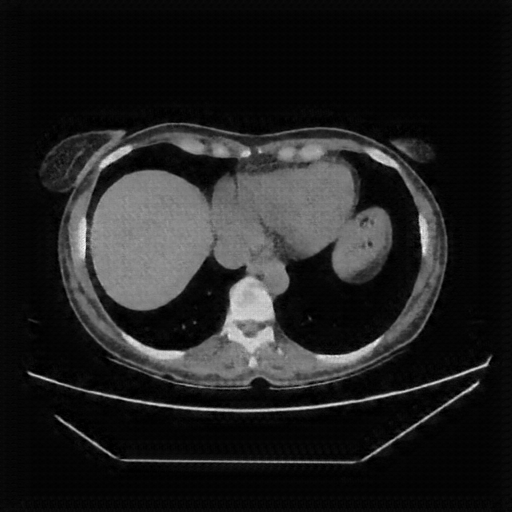

Generated VENOUS CT scan (A→B translation)

Mediastinum window (WL 40, WW 400 β†’ Low βˆ’160, High +240)